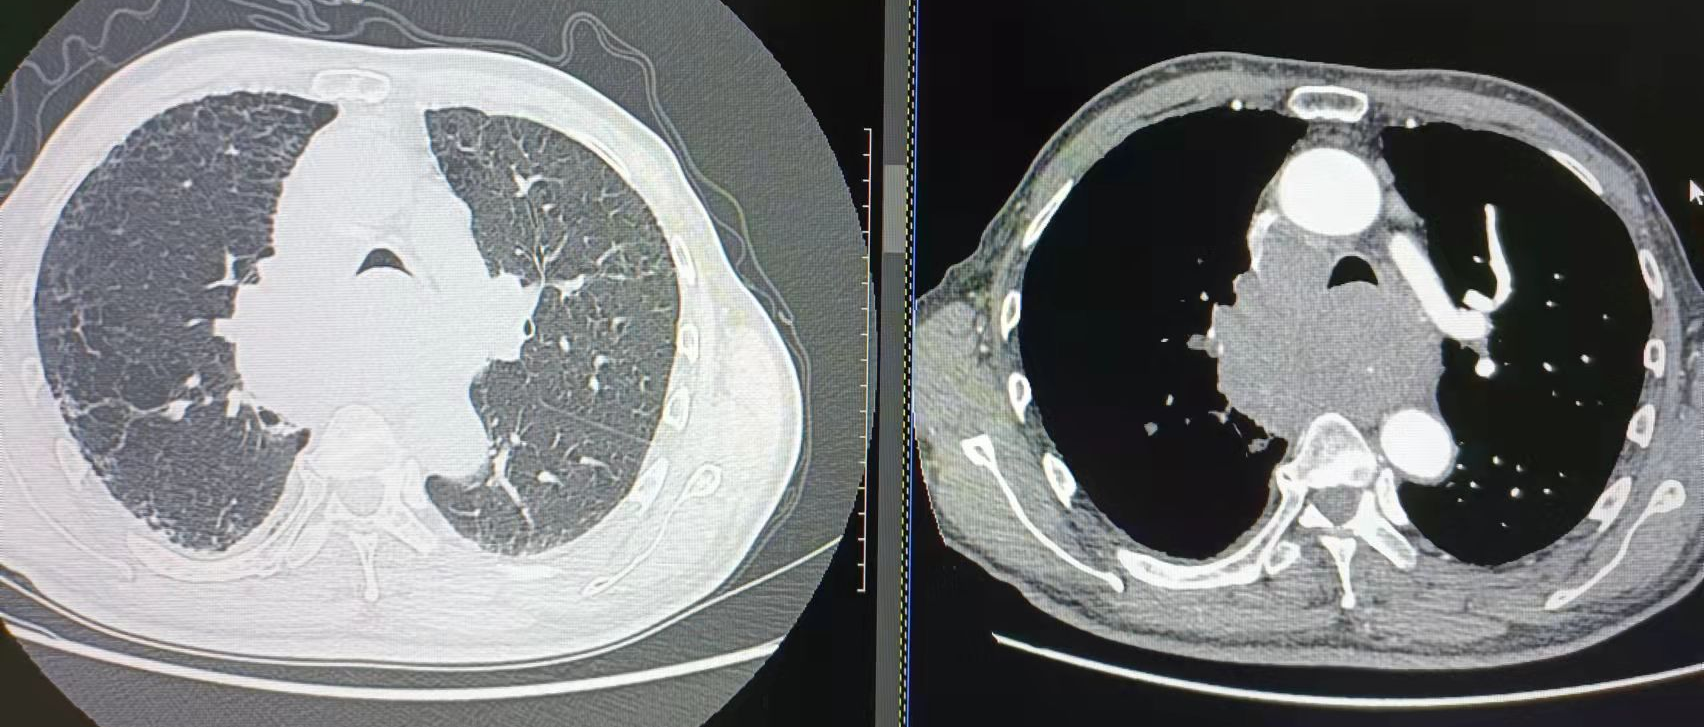

胸部CT示(11-22):气管、左主支气管受压明显变窄,右主支气管几乎完全闭塞。

大气道削瘤术后,患者病情暂时缓解,治疗远未结束,各项后续治疗措施有条不紊地持续推进。在重症医学科里,医务科组织为患者进行了多学科会诊讨论后,陈璞莹主任为患者制定了下一步诊疗方案:左总有肿物长入,右总几乎完全阻塞,需要行双气道支架置入术。但支架需要根据患者气道定制,为了做到严丝合缝,影像科章强主任帮忙测量气道直径大小。